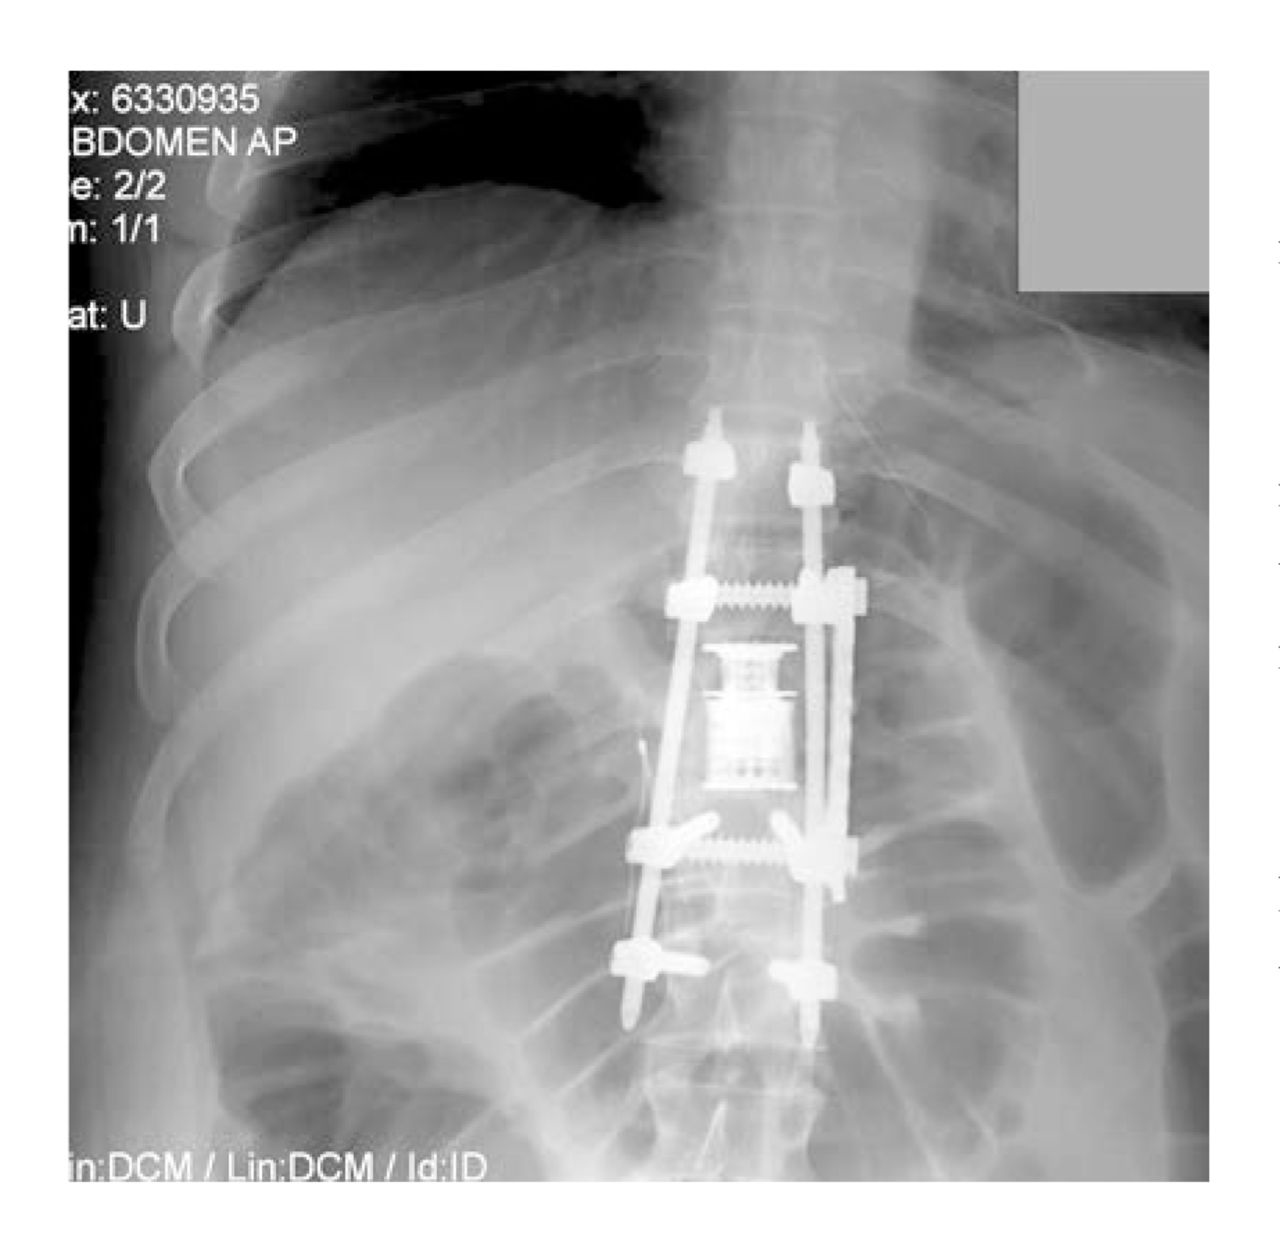

In June 2012, a 36-year-old man with paraplegia presented to the internal medicine office with the chief complaint of “I think I need my hormones checked.” He reported that he had sustained a spinal cord injury at spinal levels T10 through L2 approximately 6 months earlier after a rock climbing accident and that he had noticed several physical and mental changes since that time. He stated that he was currently attending physical therapy for rehabilitation 5 times per week but that “no matter how hard I hit it, I don't feel like I'm getting anywhere. Some days I feel like I'm going backwards.” Past medical history was notable for spinal cord injury in December 2011, which required spinal stabilization and spinal fusion of the T10-L2 vertebrae (Figure) and subsequent hospitalization. He denied any other surgical or medical history. His medications included oral hydrocodone bitartrate/acetaminophen (5 mg/325 mg), 2 tablets twice daily for pain. He denied any drug or environmental allergies. The patient expressed a feeling of loss of self, which he reported was separate from the losses engendered by his injury. Review of systems revealed fatigue, lack of motivation, poor concentration, depressed mood, unexplainable crying episodes, gynecomastia, weight loss, muscle atrophy in the legs, and absent libido. He denied hot flashes, changes in vision, or headache.

Figure.

Radiologic image of spinal stabilization and fusion in a 36-year-old man with paraplegia and hypogonadism. Hardware was placed from spinal levels T10 through L2. Gonadal innervation classically occurs at spinal levels T10 through T11.25